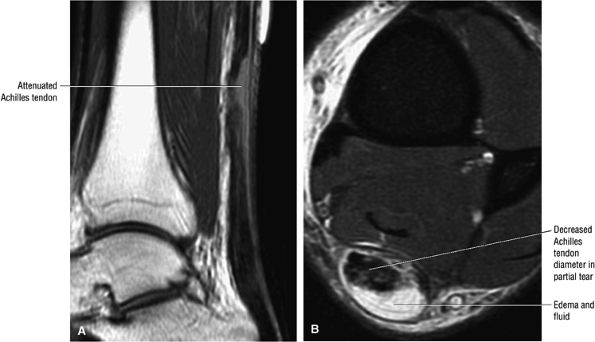

FIGURE 5.122 ● Attenuated anterior-to-posterior tendon thickness in an extensive partial Achilles tendon tear without a tendinous gap. (A) Sagittal T1-weighted image. (B) Axial FS PD FSE image.